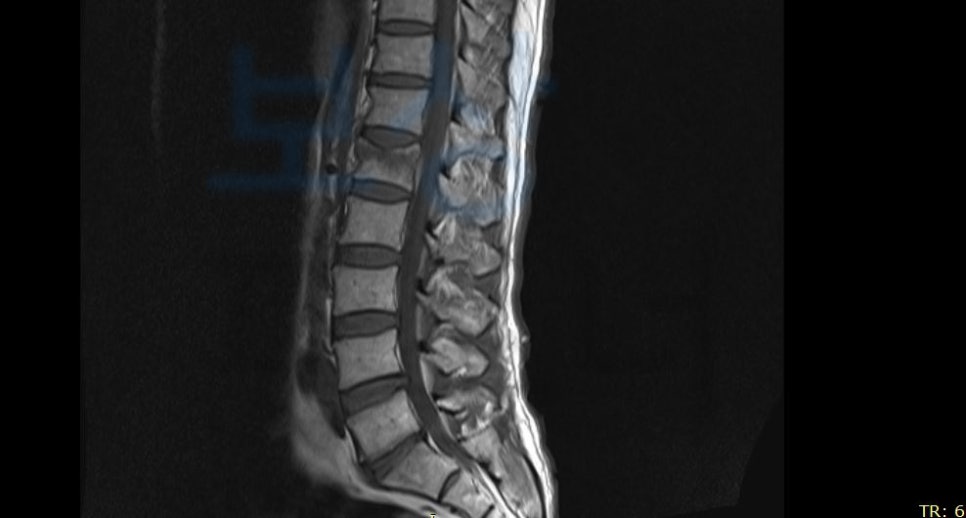

권@@님은 트럭을 정차해둔 상태에서 짐이 삐져 나와 있는 것을 발견하고 집어 넣으려다가 그대로 추락하는 사고를 당하셨습니다. 갑작스러운 사고로 인해 병원에 내원하여 정밀검사를 받아보니

요골 하단의 골절 과 함께 L1부위의 골절 즉 요추 1번의 척추압박골절 진단을 받으셨죠. 보존적 치료를 진행하여 척추뼈가 다 유합되어도 많은 분들이 수개월간 통증을 호소하시는데요, 개인적으로 가입하신 보험에서 보상 받을 수 있습니다.